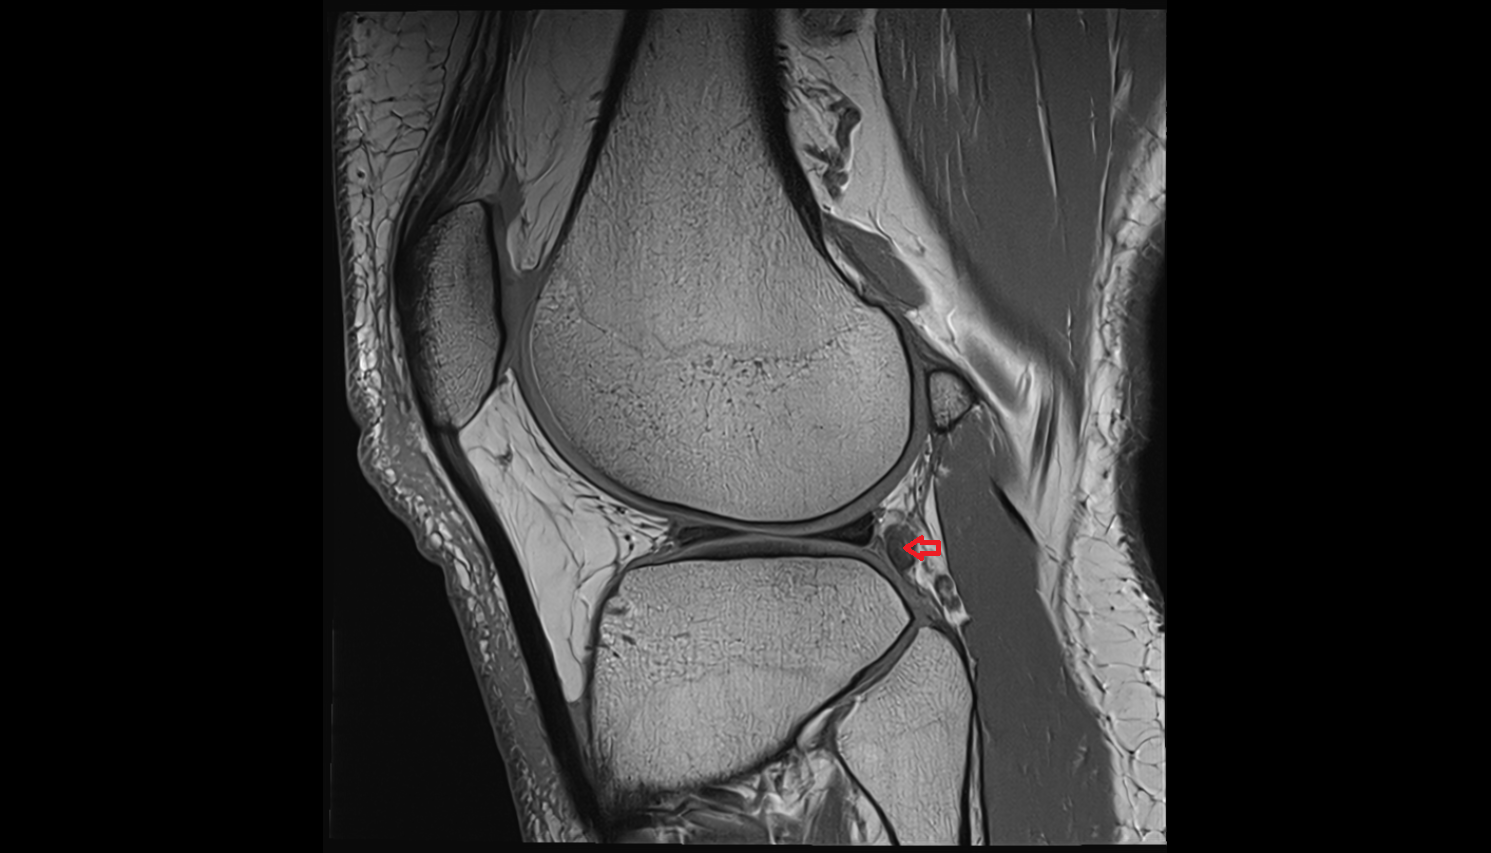

- Medial collateral ligament

- Anterior cruciate ligament

- Posterior cruciate ligament

- Medial meniscus

- Lateral meniscus